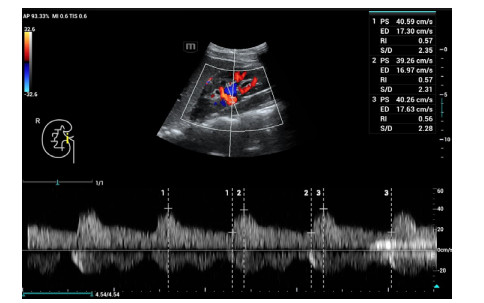

肾脏超声检查方法:所有超声检查在患者入住ICU当天由同一位超声诊断医生完成;患者取平卧位,将SC6-1s探头置于右腰部腋后线附近横切发现肾脏,再行肾脏冠状切面扫查,清晰显示上、下两极轮廓及肾内结构后启用彩色多普勒功能键显示肾脏血管并应用频谱多普勒分别于肾髓质与肾柱间检测叶间动脉(图 1)、肾窦内检测段动脉(图 2)、肾门处检测主动脉(图 3),选择3个相似且完整的频谱测量其阻力指数(resistance index, RI)值并取平均。多普勒超声检查时,声束与血流夹角尽量小于20°,取样容积在2~4 mm之间。

| 图 3 右肾主动脉RI值 Fig 3 The resistance index (RI) of the right renal aorta artery |